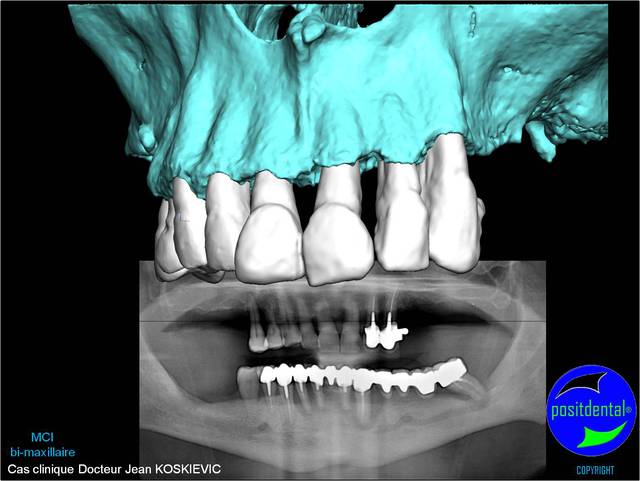

05/05/2011 à 19h19

rendu 3D maxillaire sup, pano et photo